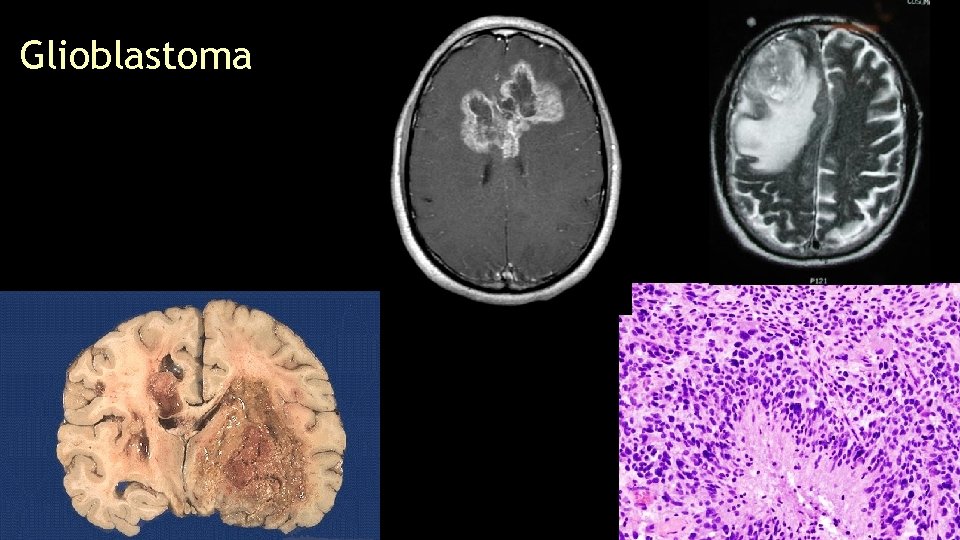

Glioblastoma